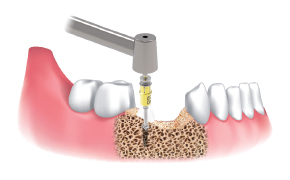

A Clinical Case using Ø3.5/4.0 Harvesting Drill

by Dr. Soohong Kim, DDS, Ph.D

Drilling at 300 rpm with irrigation was carried out after marking implant and harvesting position.

The Silicone Shield was brought into close contact with various types of bone level and prevented bone chip loss.

The amount of bone taken was easily ascertained, through the transparent Silicone Shield.

The bone was transferred to bone dish after disassembling the Silicone Shield and Stopper.

The amount of the bone was much more than expected.